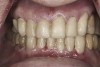

(11.) Preoperative left lateral, closed view.

Figure 11